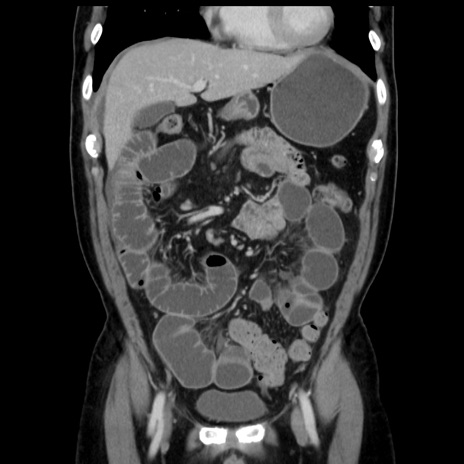

症例16(冠状断像)

【症例】 70歳代男性

【主訴】 腹痛、嘔吐

【現病歴】 約1ヶ月前より間欠的に腹痛と嘔吐あり、当院消化器内科を受診したところCTで多発する肝臓のLDAを指摘され、精査中であった。以降は消化器症状は安定していたが、2日前より嘔気と腹痛があり、同日より排便・排ガスが消失した。改善認めず、 本日、救急外来を受診した。

【既往歴】 大腸ポリープ切除後。

【身体所見】意識清明・会話良好、BT 36.3℃、BP 127/80mmHg、 P 80bpm、腹部:膨満あり、平坦・軟、上腹部正中および下腹部正中に圧痛あり、反跳痛なし、筋性防御なし。

【データ】WBC 7200、CRP 0.77